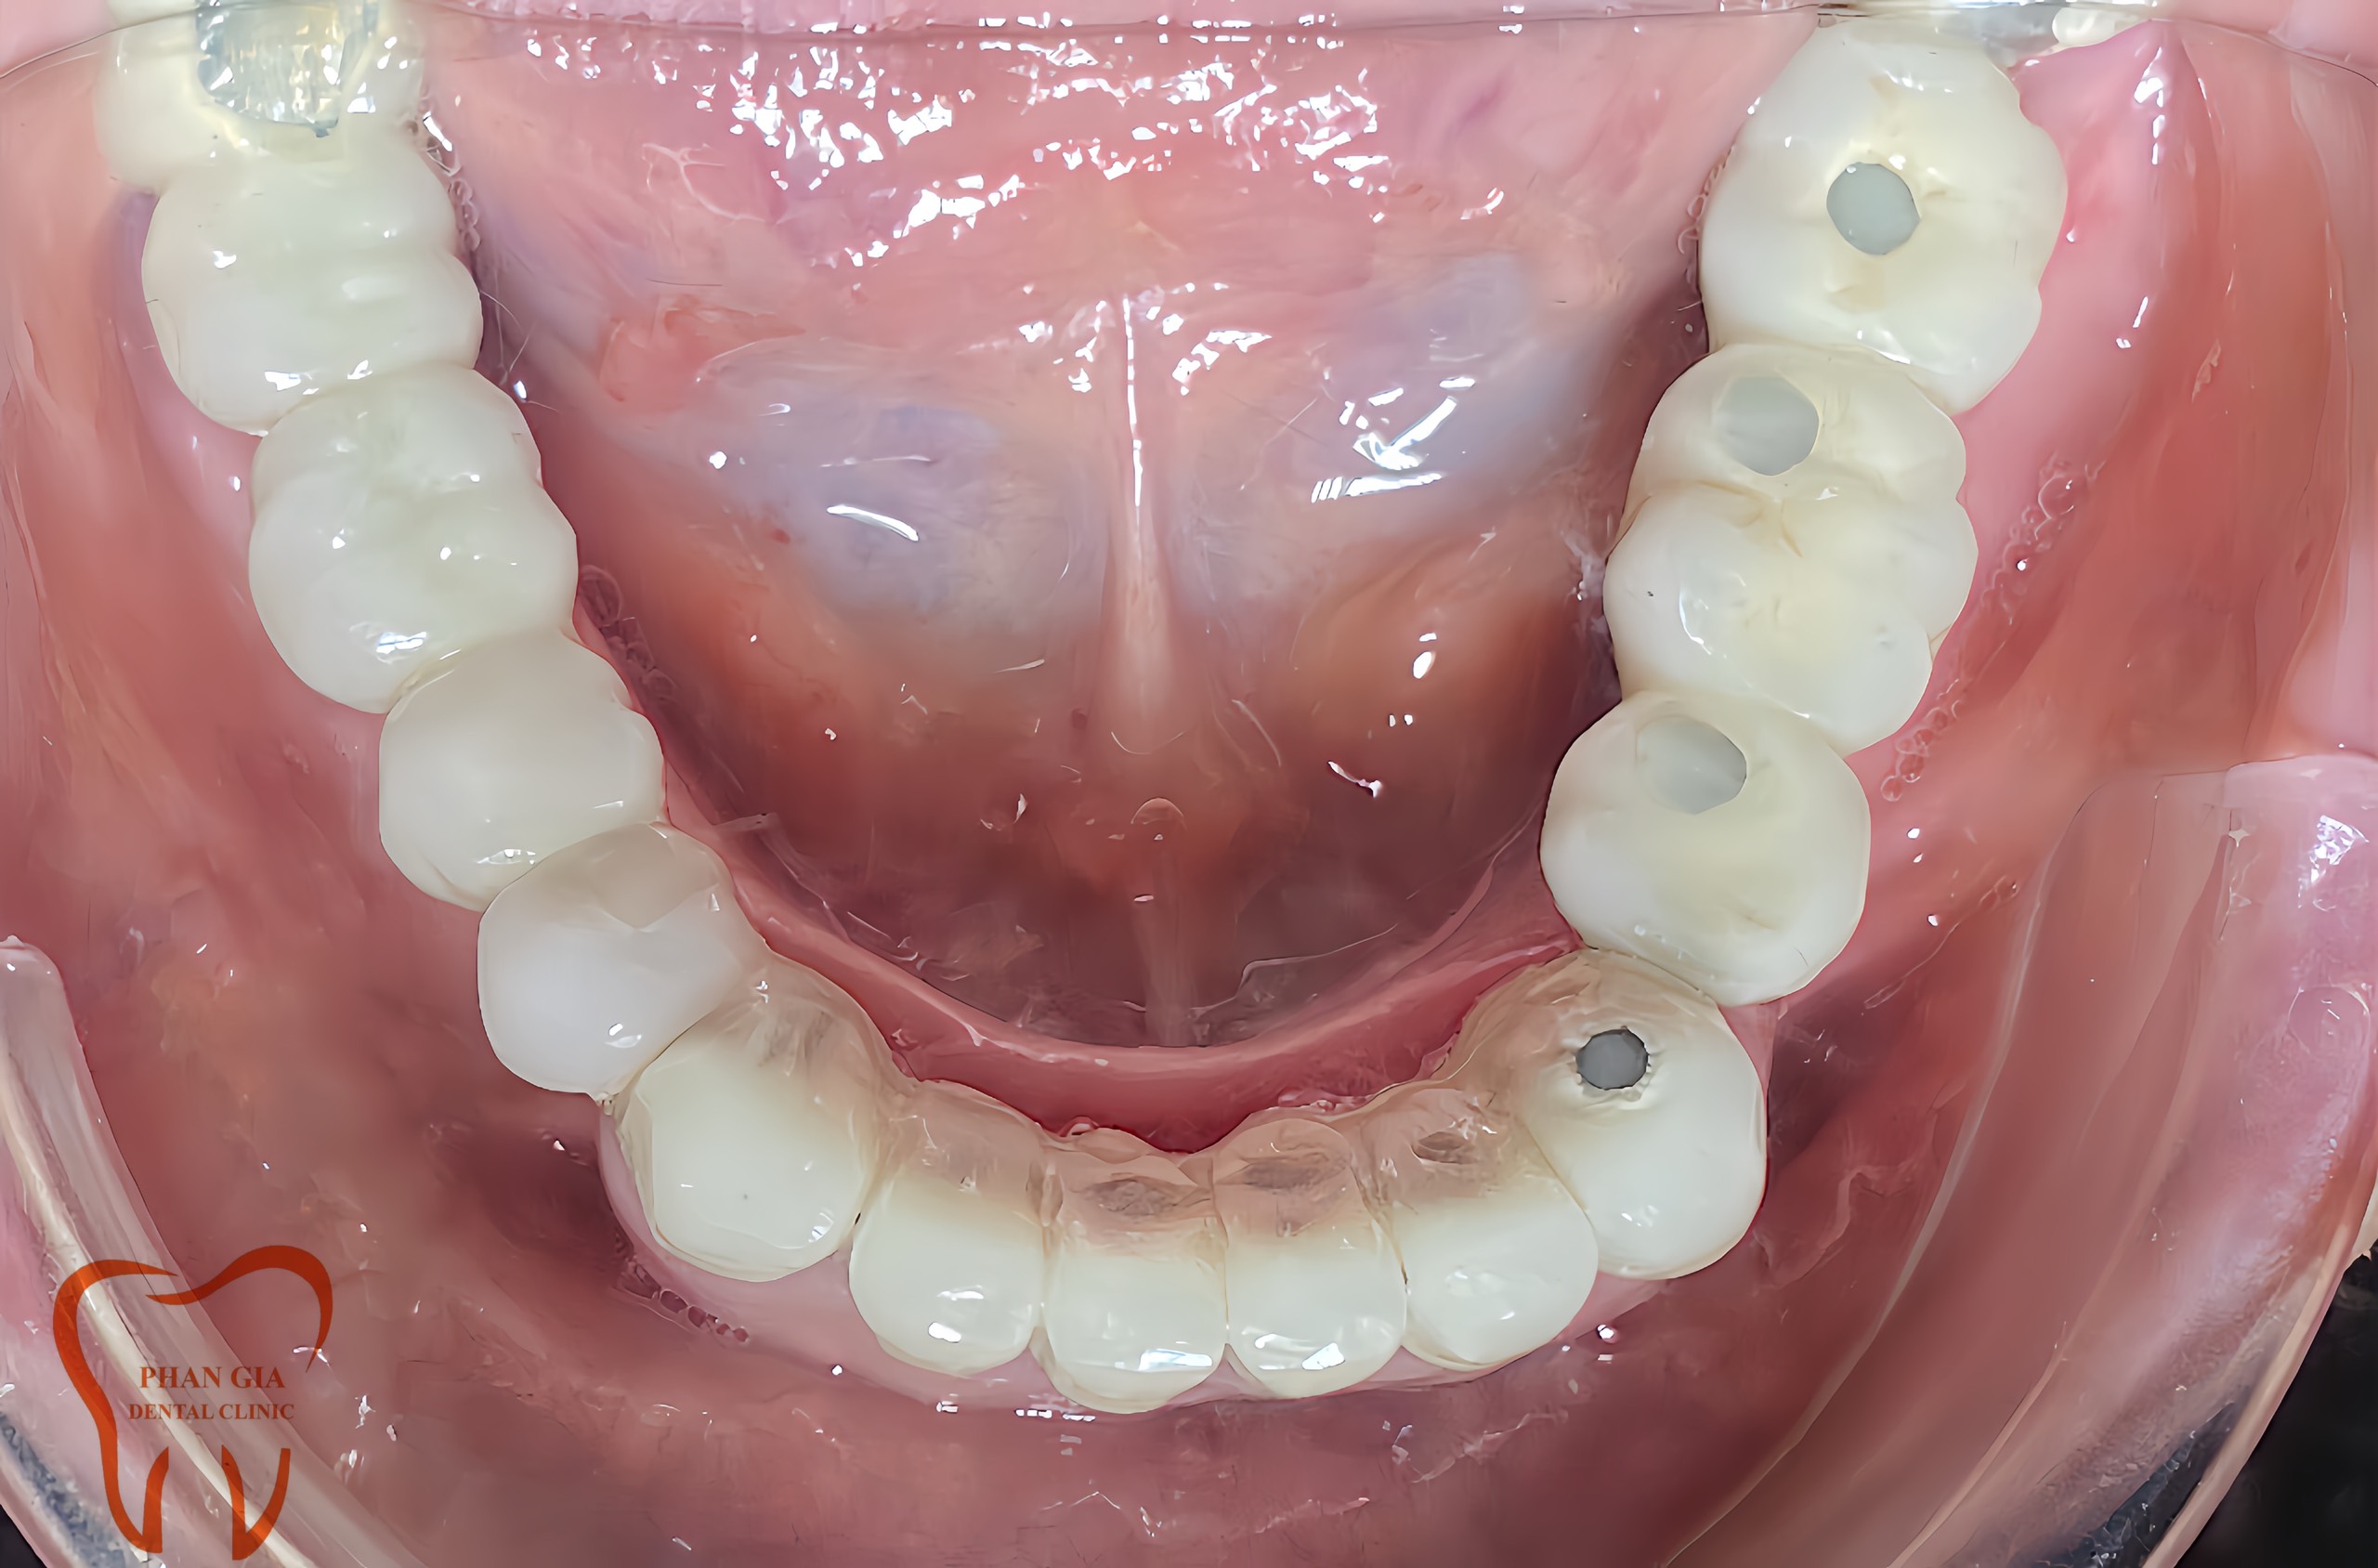

Hình ảnh minh họa hoàn thiện case cấy ghép implant và làm cầu rcầg trên implant

Chú Q một case viêm nha chu vùng răng cối phân hàm 2 và 4 gây tụt nướu lộ chân răng, răng lung lay nhiều bắt buột phải nhổ bỏ . Khi nhổ đi dĩ nhiên không còn răng ăn nhai nữa, với tư tưởng không đeo hàn tháo lắp, muốn lựa chọn phương pháp phục hình cố định chú đã chốt đơn 6 trụ implant để làm lại răng đã mất phục hồi lại chức năng ăn nhai của răng hàm.

![]() |